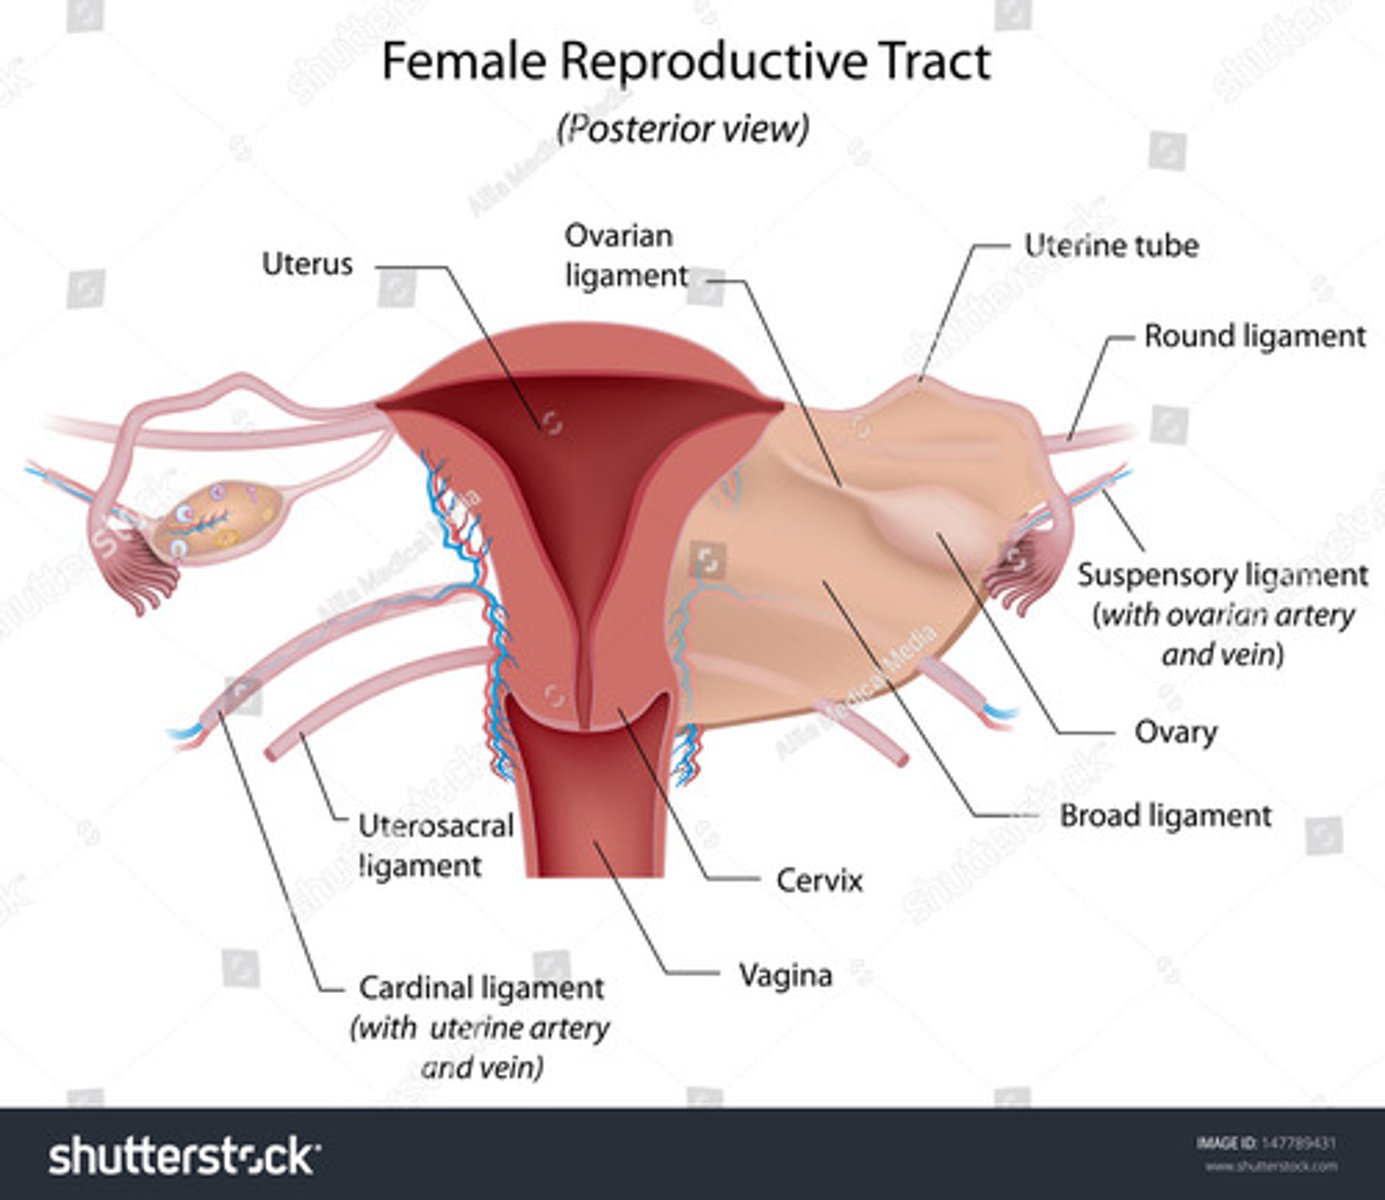

The broad ligaments extend between the ___ and ___

uterine body; ovary

What is positioned between the 2 layers of the broad ligaments?

fallopian tubes

round ligament

ovarian ligament vascular structures

The round ligaments are located ___ to the fallopian tubes and insert into the ___ to help maintain the ___ of the uterus

anteroinferior; labia majora; position

The ovarian ligaments are located ___ at the ___ of the uterus

bilaterally; cornua

The suspensory ligaments extend from the ___ to the ___

infundibulum; pelvic sidewall